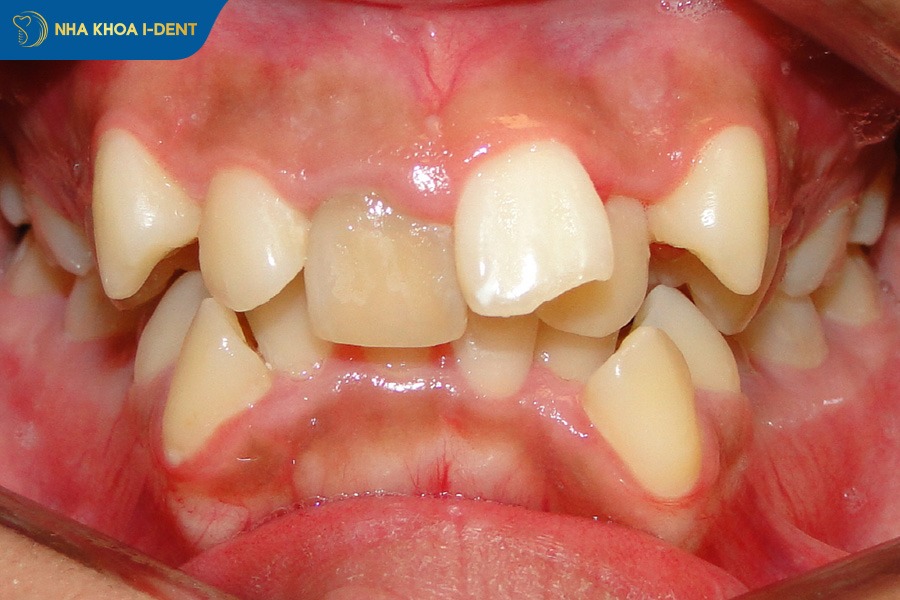

2.4. Răng mọc lệch lạc và chen chúc

Răng mọc lệch lạc hoặc chen chúc là tình trạng các răng không đủ khoảng để mọc đúng vị trí, dẫn đến hiện tượng răng xoay nghiêng, chồng chéo, cao thấp không đều hoặc mọc sai trục.

Răng mọc chồng chéo khiến bạn khó vệ sinh đặc biệt ở các kẽ răng hẹp, làm tăng nguy cơ mảng bám, sâu răng, viêm nướu và hôi miệng. Khi răng nằm sai vị trí thì lực nhai cũng không được phân bổ đồng đều dễ dẫn đến mòn răng, ê buốt hoặc đau khớp thái dương hàm về lâu dài.

Niềng răng sắp xếp lại các răng chen chúc, tạo khoảng phù hợp trên cung hàm và đưa răng về đúng vị trí. Sau khi điều trị răng sẽ đều đẹp, khớp cắn ổn định và việc ăn nhai, vệ sinh răng miệng cũng trở nên dễ dàng hơn. Tùy vào mức độ chen chúc mà bác sĩ có thể chỉ định tạo khoảng, mài kẽ nhẹ hoặc nhổ răng để đạt hiệu quả chỉnh nha cao.

Nên niềng răng để sắp xếp lại các răng chen chúc.